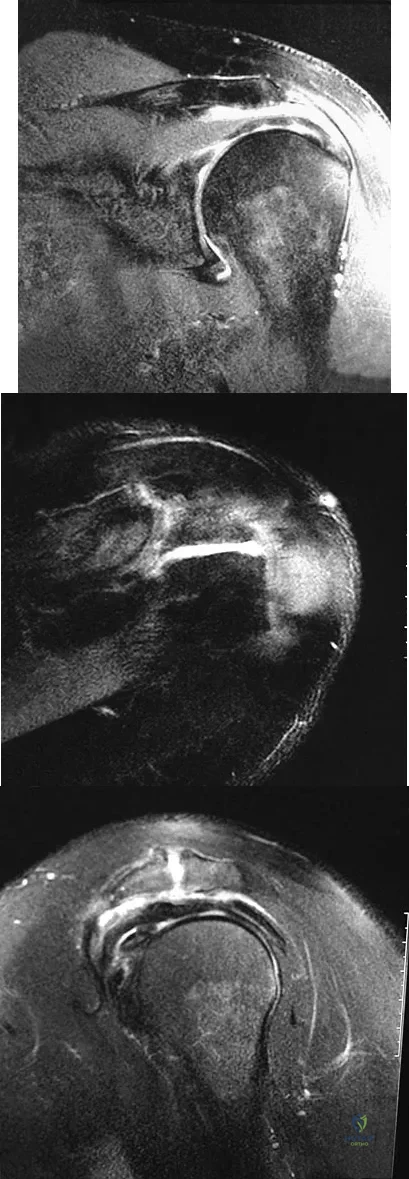

Question 68

Figures 26a through 26c show the MRI scans of a 47-year-old man who underwent arthroscopic shoulder surgery 6 months ago and continues to have pain despite a prolonged course of rehabilitation. Management should now consist of

Explanation